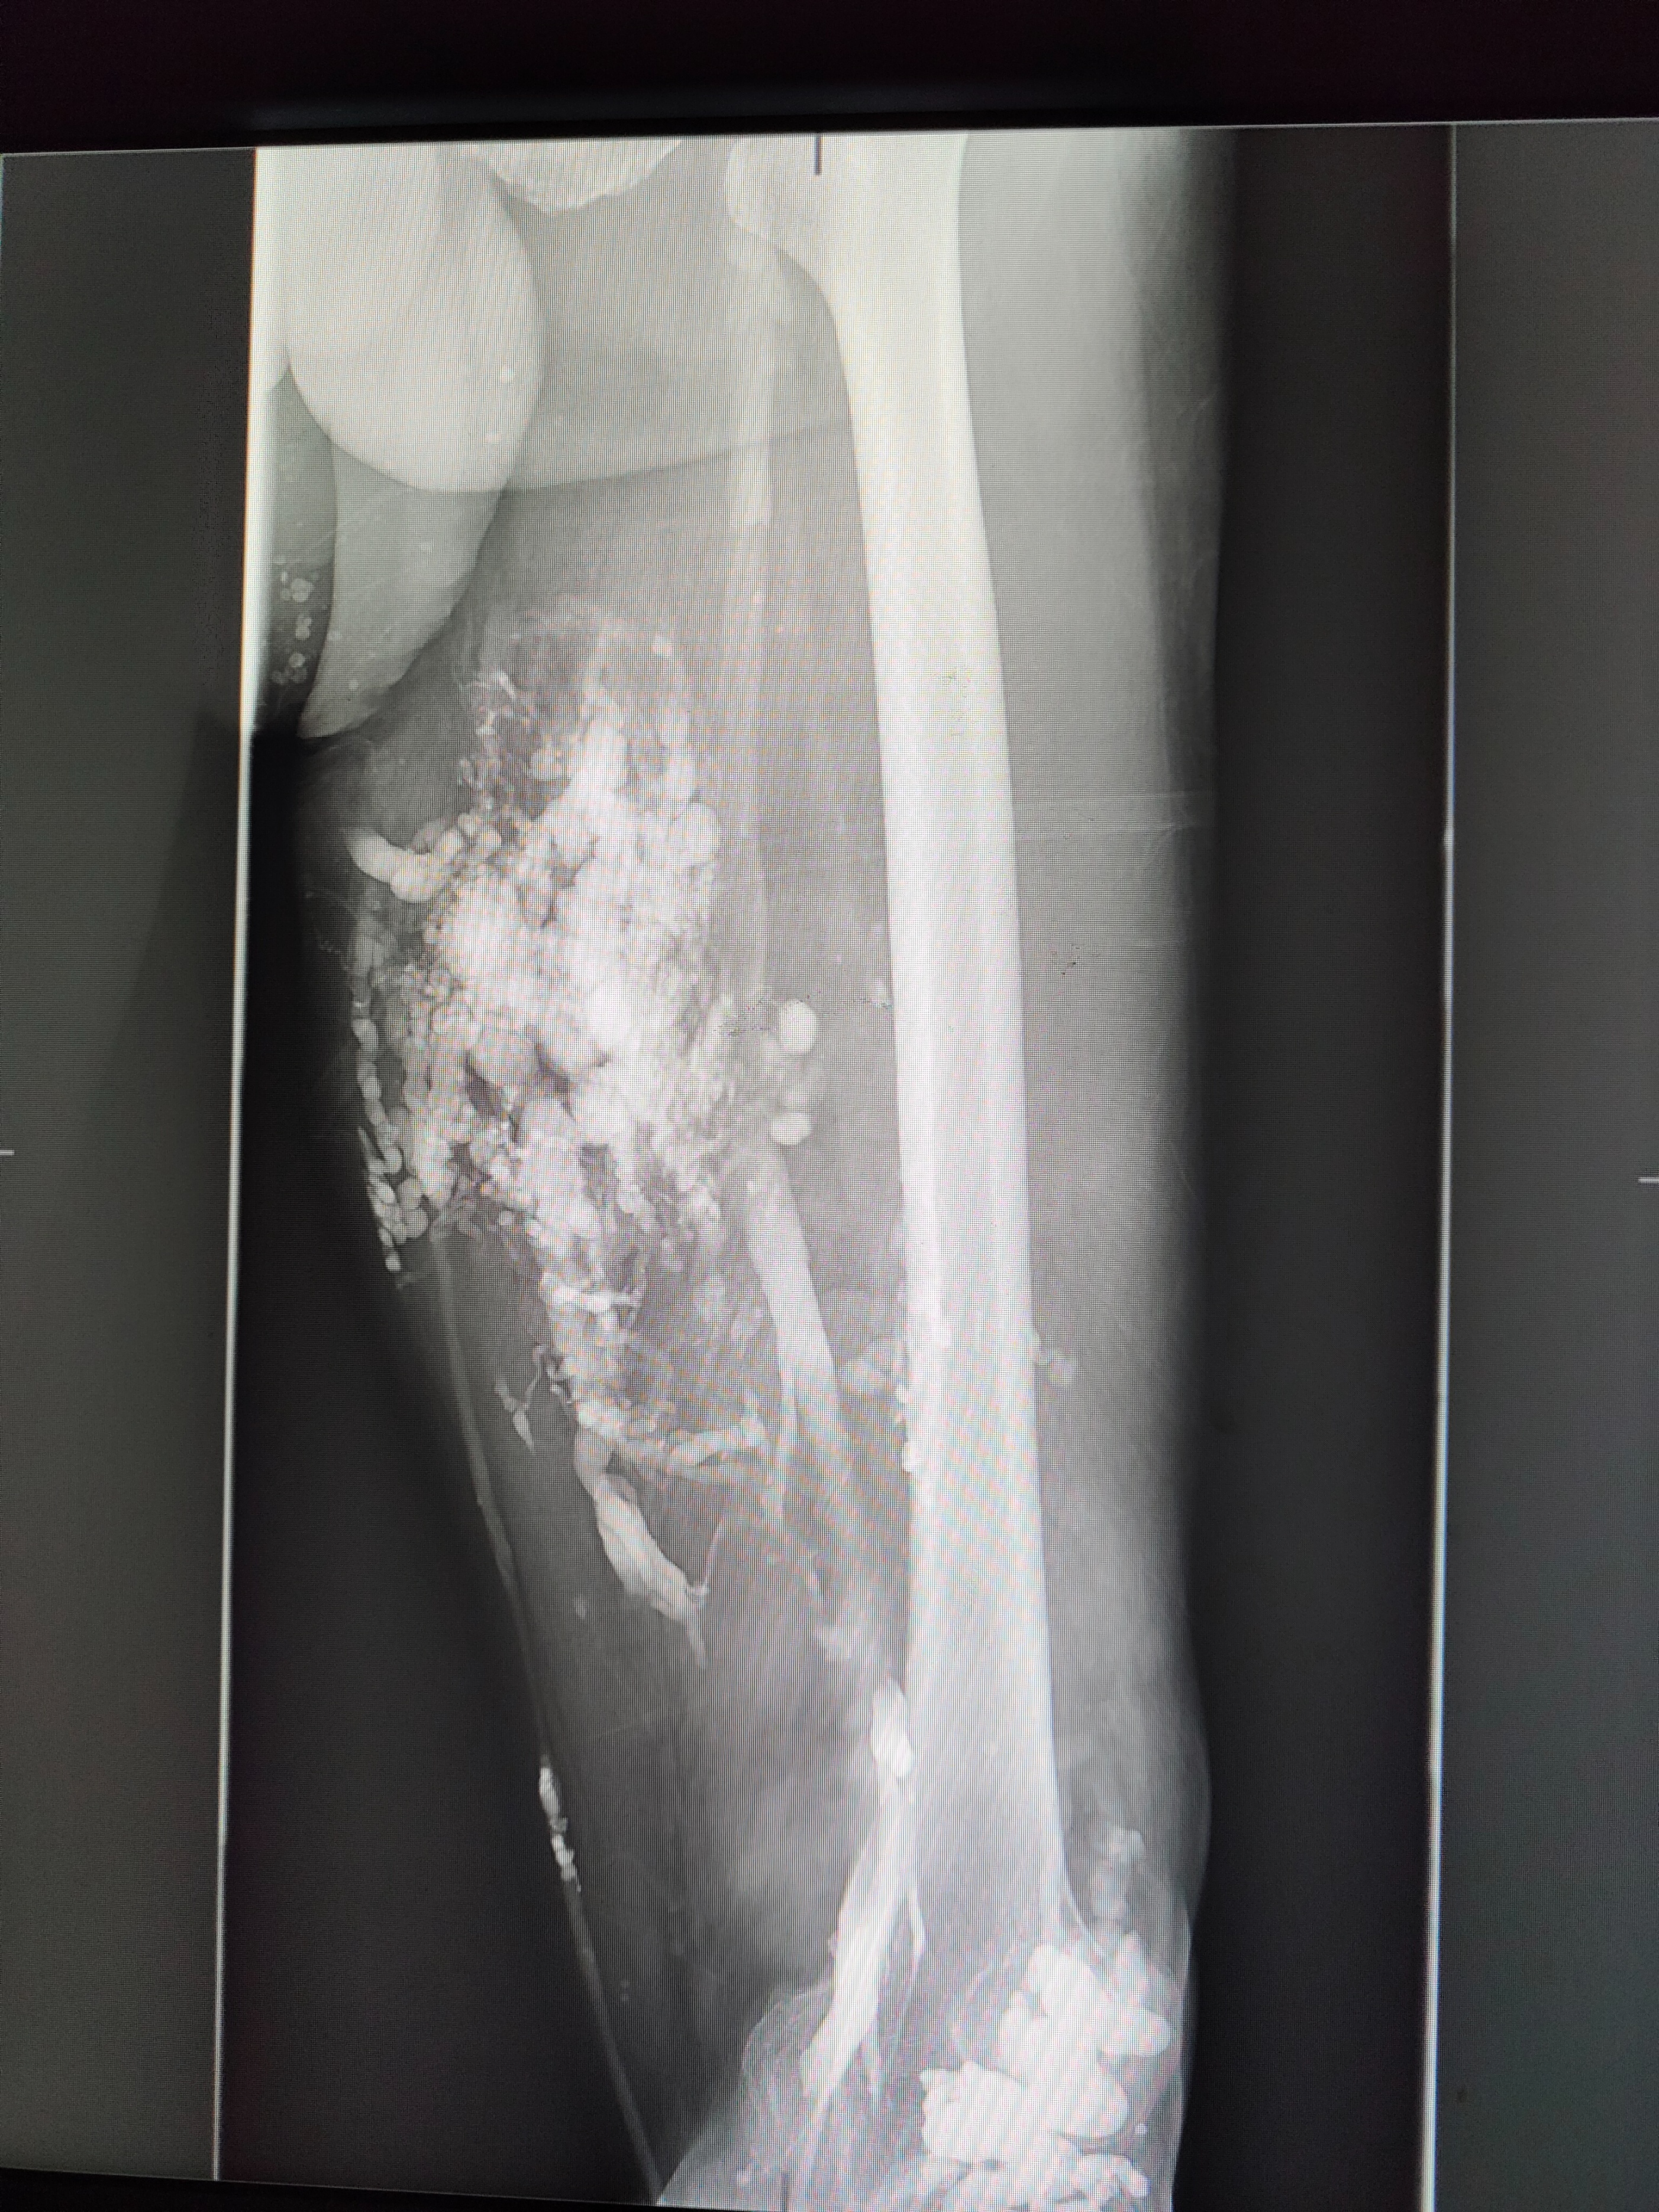

图3 静脉造影提示下肢静脉畸形,血管分布杂乱无序